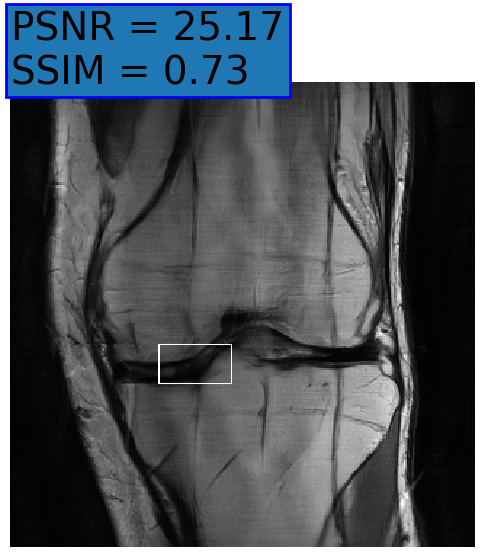

(e) NPB-REC Std.

Figure 6: Examples of reconstruction results. Rows 1, 3, and 5: The reference (GT) fully sampled image, the reconstructed images obtained by the three models (1-3), NPB-REC, baseline, E2E-VarNet trained with Dropout, and the Std. map derived from our method for example from the knee dataset, the brain dataset, and the brain dataset sampled with radial mask L=50𝐿50L=50, respectively. Rows 2, 4, and 6: The corresponding annotated ROIs of the cartilage, edema, and nonspecific white matter lesion respectively.

Table 2: Reconstruction accuracy for the knee dataset. Rows top to bottom: PSNR and SSIM metrics calculated on the annotated anatomical ROIs (denoted by ’A’), and the whole physical images (denoted by ’W’) with masks of acceleration rates R=4𝑅4R=4, R=8𝑅8R=8 and R=12𝑅12R=12, respectively.

NPB-REC Baseline Dropout

R PSNR SSIM PSNR SSIM PSNR SSIM

4 W 36.21±5.57plus-or-minus36.215.5736.21\pm 5.57 0.912±0.0963plus-or-minus0.9120.09630.912\pm 0.0963 37.43±5.58plus-or-minus37.435.5837.43\pm 5.58 0.912±0.098plus-or-minus0.9120.0980.912\pm 0.098 37.68±4.81plus-or-minus37.684.81\mathbf{37.68\pm 4.81} 0.912±0.091plus-or-minus0.9120.091\mathbf{0.912\pm 0.091}

A 24.31±6.99plus-or-minus24.316.9924.31\pm 6.99 0.855±0.214plus-or-minus0.8550.2140.855\pm 0.214 25.28±6.71plus-or-minus25.286.7125.28\pm 6.71 0.861±0.215plus-or-minus0.8610.2150.861\pm 0.215 25.57±7.13plus-or-minus25.577.13\mathbf{25.57\pm 7.13} 0.862±0.218plus-or-minus0.8620.218\mathbf{0.862\pm 0.218}

8 W 32.38±4.46plus-or-minus32.384.46\mathbf{32.38\pm 4.46} 0.849±0.108plus-or-minus0.8490.108\mathbf{0.849\pm 0.108} 30.3±4.14plus-or-minus30.34.1430.3\pm 4.14 0.825±0.103plus-or-minus0.8250.1030.825\pm 0.103 31.63±4.38plus-or-minus31.634.3831.63\pm 4.38 0.836±0.096plus-or-minus0.8360.0960.836\pm 0.096

A 20.77±6.18plus-or-minus20.776.18\mathbf{20.77\pm 6.18} 0.716±0.332plus-or-minus0.7160.332\mathbf{0.716\pm 0.332} 19.02±5.86plus-or-minus19.025.8619.02\pm 5.86 0.668±0.342plus-or-minus0.6680.3420.668\pm 0.342 20.18±5.74plus-or-minus20.185.7420.18\pm 5.74 0.691±0.324plus-or-minus0.6910.3240.691\pm 0.324

12 W 29.17±4.23plus-or-minus29.174.23\mathbf{29.17\pm 4.23} 0.784±0.104plus-or-minus0.7840.104\mathbf{0.784\pm 0.104} 25.3±5.66plus-or-minus25.35.6625.3\pm 5.66 0.724±0.115plus-or-minus0.7240.1150.724\pm 0.115 28.23±4.89plus-or-minus28.234.8928.23\pm 4.89 0.766±0.102plus-or-minus0.7660.1020.766\pm 0.102

A 17.85±5.56plus-or-minus17.855.56\mathbf{17.85\pm 5.56} 0.573±0.361plus-or-minus0.5730.361\mathbf{0.573\pm 0.361} 15.03±7.03plus-or-minus15.037.0315.03\pm 7.03 0.448±0.414plus-or-minus0.4480.4140.448\pm 0.414 16.95±6.27plus-or-minus16.956.2716.95\pm 6.27 0.534±0.364plus-or-minus0.5340.3640.534\pm 0.364

Fig. 6 depicts the reconstruction results obtained by (1) our NPB-REC approach, (2) the baseline, and (3) Monte Carlo Dropout, for examples of both the knee (row 1) and the brain (rows 3 and 5) datasets. The first two examples were obtained by the models that trained on brain data and were tested on knee data (row 1) and vice versa (row 3). In knee images, all three models exhibit minimal differences in handling pronounced folding artifacts. However, our approach demonstrates superior reconstruction performance for anatomical annotations or pathological regions, labeled by radiologists, in terms of both PSNR and SSIM. The last example is a reconstructed brain image that was obtained by the three models, where the k-space input is undersampled by a radial mask with L=50𝐿50L=50. Table 2 presents the mean PSNR and SSIM metrics, calculated over the whole inference knee dataset, for the three models that were trained on brain data. The NPB-REC method shows a considerable improvement in the generalization ability on knee data for higher acceleration rates R=8𝑅8R=8 and R=12𝑅12R=12 in both annotation regions and the whole images. However, both the baseline and Dropout methods show a slight improvement in the metrics in the case of a small acceleration rate R=4𝑅4R=4. Table 3 shows the results of the inverse experiment, i.e. calculating the mean PSNR and SSIM metrics over the whole brain inference set for the three models that were trained on knee data only. The generalization capability of the three models in the case of an anatomical distribution shift from the knee to the brain is better than the opposite scenario. This is not only measured quantitatively by the SSIM and PSNR metrics, but also visible in the predicted reconstructions. For instance, the brain MRI reconstructed images exhibit fewer artifacts than the produced knee images, as shown in row 1 vs. row 3 in Fig. 6.